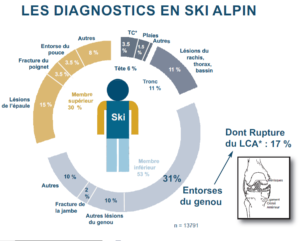

Rupture du LCA (ligament croisé Antérieur)